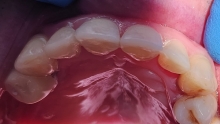

Clinica LUY ESTHETIC ART defineste parodontoza ca fiind rezultatul direct al placii dentare, care se depune pe suprafata dintilor, dar si in apropiere de marginea gingivala. Aceasta boala duce la pierderea dintilor, chiar daca ei sunt aparent sanatosi si nu prezinta carii. Edentatiile, afecteaza vorbirea, aspectul, dar si capacitatea de a mesteca.

– retractii gingivale cu expunerea radacinilor dentare;

Recomandam controale periodice (3-6 luni) pentru igienizari profesionale: detartraj, periaj dentar, air-flow etc. Aceste operatiuni asigura sanatatea gingiei, iar osul alveolar si ligamentele parodontale isi pastreaza integritatea.